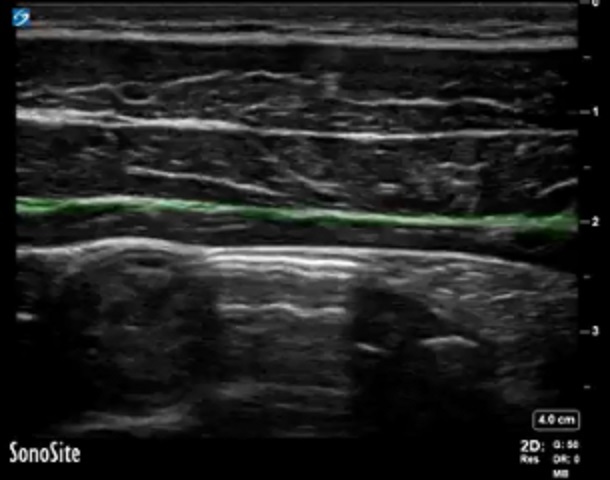

Bild: TAP, Faszie zwischen M. obliquus internus und M. transversus abdominis

Markierter Bereich: Faszie zwischen M. obliquus internus und M. transversus abdominis